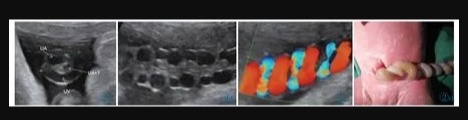

11 例中孕期超聲均可見2 條UA(膀胱水平橫切面顯示2 條UA 血流信號),超聲最后一次提示可見2 條UA 的平均孕周為(31.2±3.1)周。11 例超聲首次提示UA 數(shù)目異常(表現(xiàn)為膀胱水平橫切面UA彩色多普勒僅顯示1 條UA 及血流信號,另一側(cè)血流信號消失)的平均孕周為(36.7±2.8)周,6 例(54.4%)為膀胱左側(cè)血流信號消失,5 例(45.5%)為膀胱右側(cè)血流信號消失。7 例(63.6%)孕晚期超聲首次即提示單條UAT,這7 例臍帶游離段橫切面二維灰階圖像均顯示3 個管腔結(jié)構(gòu),其中1 條UA 內(nèi)可見稍高回聲填充且血流信號消失(圖1);1 例(9.1%)在孕34+4周提示單臍動脈,在孕37 周超聲隨訪中糾正診斷為單條UAT,因超聲提示臍帶高度螺旋,且在臍帶橫切面下見臍靜脈呈“C 形”包繞2條UA,1 條UA 內(nèi)存在血栓回聲(圖2),該病例同時合并胎兒生長受限;3 例(27.3%)整個孕期均提示單臍動脈,回顧其既往中孕期超聲均見2 條UA,晚孕期超聲發(fā)現(xiàn)1 條UA 內(nèi)存在血栓回聲(圖3)。

圖1a 臍帶橫切面。1 條臍靜脈管腔大,內(nèi)為無回聲。2 條UA 管腔小,栓塞側(cè)內(nèi)為稍高回聲(血栓回聲),通暢側(cè)內(nèi)為無回聲。圖1b 臍帶橫切面。臍靜脈及通暢側(cè)UA 內(nèi)見方向相反的血流信號,栓塞UA內(nèi)無血流信號(箭頭所示)。圖1c 臍帶縱切面。臍靜脈內(nèi)為無回聲,栓塞UA 內(nèi)等回聲為血栓(箭頭所示)。圖1d 臍帶縱切面。臍靜脈內(nèi)可見血流信號,栓塞UA 內(nèi)無血流信號。圖1e 通暢側(cè)UA:舒張末期血流流速增加,S/D 和PI 偏低。圖1f MCA:舒張末期血流流速增加,PI 值降低。Figure 1a.Cross section of cord.No echo is shown in the lumen of umbilical vein(the larger one).Two UAs have smaller lumens,and hyperecho is found in the occluded UA(thrombus).Figure 1b.Cross section of cord.Opposite blood flows are shown in umbilical vein and the normal UA,and no blood flow signal is shown in the occluded UA(as indicated by the arrow).Figure 1c.Longitudinal section of cord.There is no echo in umbilical vein and the arrow indicates the thrombus in the occluded UA.Figure 1d.Longitudinal section of cord.There is blood flow in umbilical vein and no blood flow in the occluded UA.Figure 1e.The unobstructed UA: the end diastolic blood flow velocity increases;S/D and PI decreases.Figure 1f.MCA: the end diastolic blood flow velocity increases;PI decreases.

圖2 a 臍帶橫切面。臍靜脈呈“C 形”包繞2 條UA,1 條UA 內(nèi)存在血栓回聲(T:血栓)。圖2b~2d 臍帶高度螺旋。Figure 2 a.Cross section of umbilical cord.One clogged UA is in parallel with the other unobstructed one and both of them are surrounded by umbilical vein(T: thrombi).Figure 2b~2d.Hyper-coiling of umbilical cord.

圖3 誤診為單臍動脈病例的超聲圖像。圖3a:孕24+4 周,膀胱兩側(cè)均可見UA 血流信號;圖3b:孕37+1 周,膀胱一側(cè)UA 血流信號消失;圖3c:臍帶橫切面見臍靜脈呈“C 形”包繞2 條UA,箭頭所示其中1 條UA 管腔細(xì)小,內(nèi)為稍高回聲(血栓)填充。圖4 臍帶病理(HE 染色)。UA 內(nèi)見血栓形成,管壁彈力纖維梗死。Figure 3.Ultrasonography misdiagnosed as single umbilical artery.Figure 3a: At 24+4 weeks,the blood flow of two UAs is seen in both sides of bladder.Figure 3b: At 37+1 weeks,only one UA is seen in the level of bladder.Figure 3c: In the cross section of umbilical cord,two UAs are surrounded by umbilical vein.As indicated by the arrows,one UA has smaller lumen which is filled with a slightly higher echo(thrombi).Figure 4.The pathological finding of umbilical cord (HE stain).The UA lumen is filled with thrombi.The necrosis of elastic fibers are found in arterial wall.